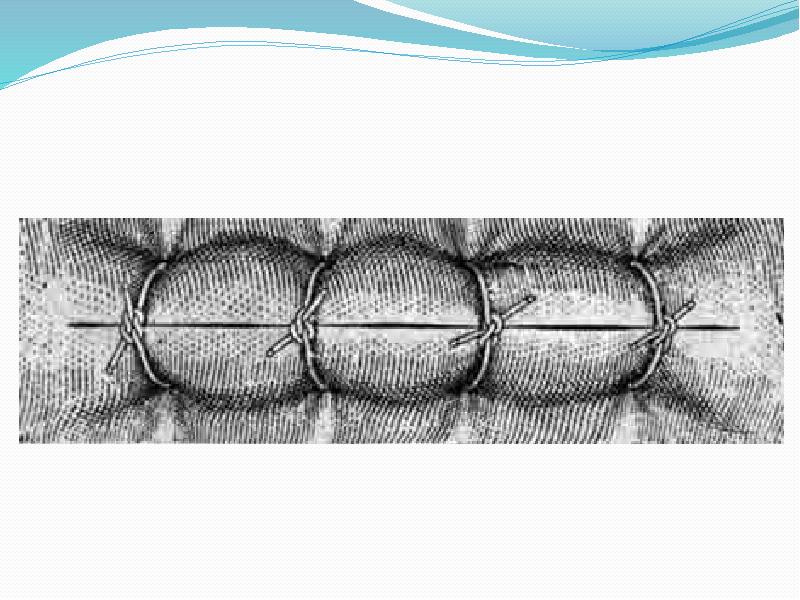

- 19. Простой узловой шов 1. Хирургическим пинцетом фиксируют сшиваемый край раны с

- 20. Схема проведения нити

- 21. Схема направления тканей